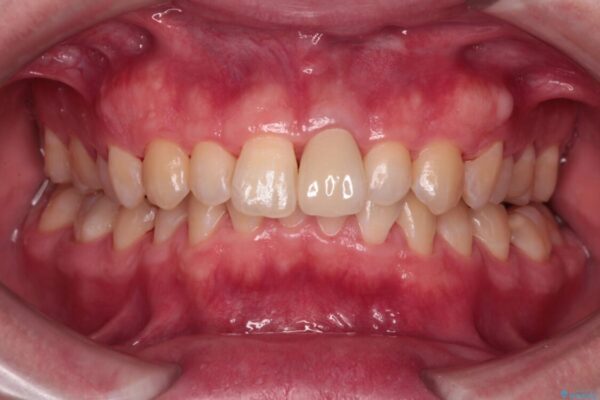

治療後

• 変色した前歯をオールセラミッククラウンに 治療後画像

神経を取り除いた歯は時間とともに変色してきます。

クリーニングやホワイトニングでは改善できないため、オールセラミッククラウンなどによる補綴治療が必要となります。